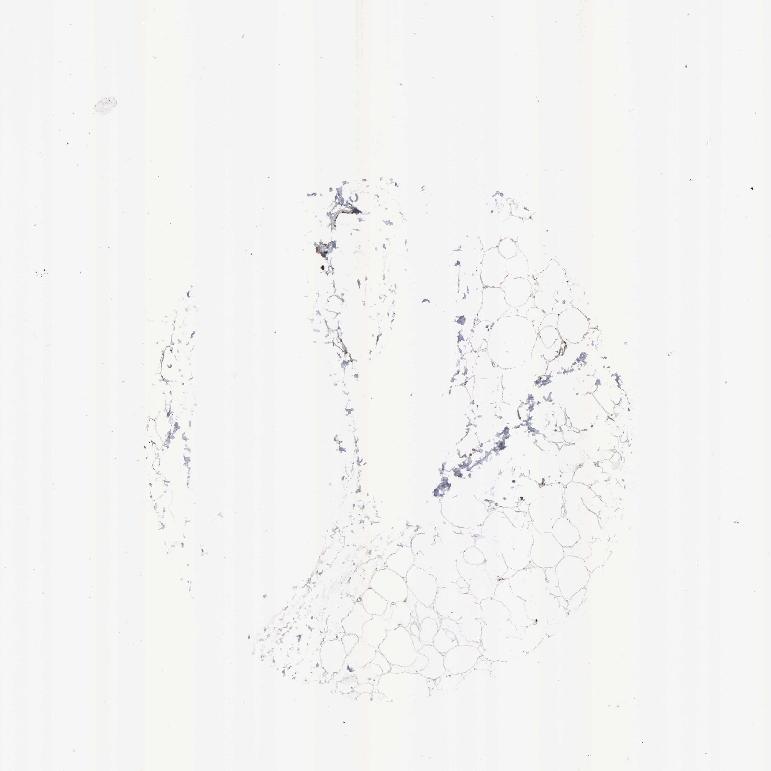

SOFT TISSUE 1 - Antibody stainingi

Antibody staining in the annotated cell types in the current human tissue is reported as not detected, low, medium, or high, based on conventional immunohistochemistry profiling in selected tissues. This score is based on the combination of the staining intensity and fraction of stained cells.

Each image is clickable and will lead to virtual microscopy that enables deeper exploration of all samples and also displays staining intensity scores, fraction scores and subcellular localization as well as patient and tissue information for each sample.

Antibody HPA000898Antibody CAB005219

Chondrocytes Medium-

Fibroblasts MediumHigh